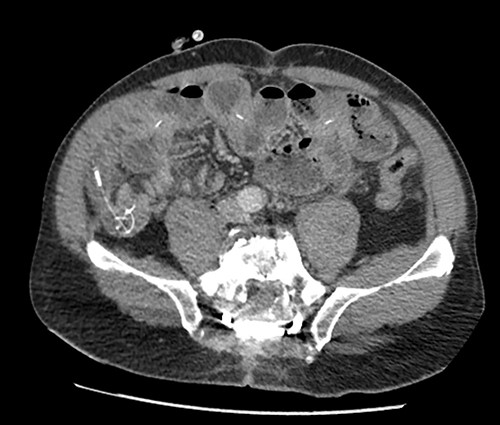

The patient presented to the emergency room for severe biliary vomiting for the past 24 h. He reported lack of gas and occlusion of his LCID pump for the past 48 h. His abdomen was distended and tender in the right flank, without guarding or signs of peritoneal irritation. Initial blood work showed an elevated white blood cell count at 13 880 103/μl and elevated CRP at 140 mg/l. Initial CT scan showed an intestinal occlusion situation in the jejunum with major gastric distention (Fig. 1). The distal tip of the catheter was visualized at the occlusion site with the evident formation of a knot at its end. There were no signs of pneumoperitoneum or intestinal hypo-perfusion. A small quantity of free fluid was seen around the jejunum. A chest X-ray revealed a right lower lobe condensation, presumed to be inhalation pneumonia. A nasogastric tube was immediately placed, the patient was started on IV fluids and broad spectrum antibiotics and was hospitalized in the surgery department. Endoscopy was initially performed, which visualized mucosal ulcerations in the duodenum, and was ultimately unsuccessful in extracting the PEG-J due to firm adherence of the jejunal catheter. Emergency surgery was then performed via a midline laparotomy. The jejunum was markedly distended with subserosal ulcerations but was otherwise viable with good color and the presence of peristalsis. There was a small amount of clear free fluid. The jejunal catheter was extracted via an enterotomy, the formation of a knot was observed at its distal end and a large occlusive bezoar had formed around the knot (Fig. 2). The enterostomy was closed transversely with a running Vicryl 3-0 suture, an abdominal drain and the NG tube were left in place.

Preoperative CT scan showing intestinal occlusion and a knot formation.